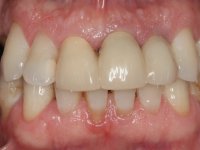

Endodontic treatments were performed and a metalic non screwed intra radicular post was placed on tooth 1.1. An alginate impression was made for laboratory confection of a reinforced acrylic provisional bridge, with teeth 1.1 and 2.2 as abutments and 2.2 as a pontic. After preparation of tooth 1.1 and root preparation of 2.1, the bridge was relined in mouth with self-polymerizable acrylic using a metal post for further retaining the prepared root canal on 2.1. Tooth 2.2 was cut at the gingival level to function as support. In the same session, the impression of the root canal of the 2.1 was made for the laboratory confection of a cast post and core. A double mixture technique with plastic tutor was used after previous canal vaseline with endodontic file and cotton. The provisional bridge was provisionally cemented and the cast post and core was made in the laboratory. Cast post and core cementation was made with resin-reinforced glass ionomer cement and the provisional bridge had to be readjusted to the new situation by removing the post at the site of 2.1. After careful surgical planning, a dental implant was placed, simultaneously with extraction of the root of tooth 2.2. The provisional bridge was placed by resting on the healing screw placed in the implant. The respected osteointegration period was 12 weeks, during which the provisional bridge was relined twice. After complete maturation of hard and soft tissues, definitive impressions were made. The gingival retraction technique was applied with an impregnated retraction cord and impression was performed using double mixture, open tray impression technique. A custom precious metal abutment implant was prepared in the lab, along with 3 metal caps to be used as infrastructures for the metal ceramic crowns. Particular care was taken in the confection of the cervical finishing line of the implant abutment, in order to follow the soft tissues emergence profile. Proof of infrastructures was done in the mouth being evaluated clinically and imagiologically. Collection of color information was done by the ceramist at the office. Ceramic was applied in the laboratory and the finished work was placed in the mouth after approval by the patient. Definitive cementation was made with resin-reinforced glass ionomer cement, and the first crown to be cemented was that of the implant, to facilitate removal of the excess.